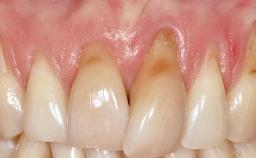

Early Implant Placement, Contour Augmentation, and Autologous Connective-Tissue Graft Using a Tunneling Technique to Replace an Upper Incisor with Generalized Gingival Recession

Variations in soft-tissue volume, evidenced either by an overabundance (Evian and coworkers 1993; Levine and McGuire1997; Dolt and Robbins 1997) or by a deficiency of soft or hard tissue can complicate implant-supported rehabilitations in the esthetic zone (Lorenzana 2008; Lorenzana and coworkers 2009). The present case illustrates the replacement of a failing upper left lateral incisor complicated by generalized severe gingival recession in the esthetic zone.

| Soft Tissue Contour and Volume | Significantly deficient |